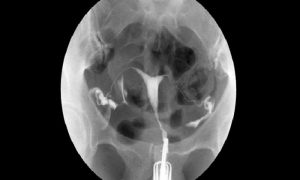

HSG ÇEKİMİ

Histerosalpingografi (HSG) veya Türkçe deyişle rahim filmi jinekolojide rahim içinin ve kanalların yapısal ve işlevsel özelliklerini incelemede ...